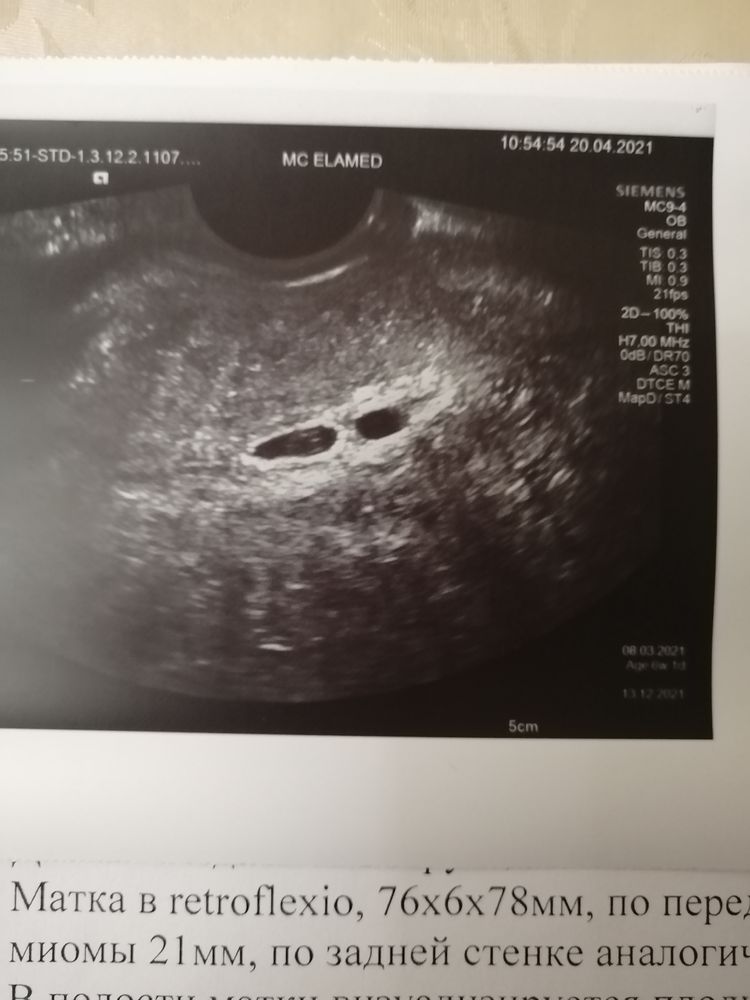

Посмотрите кто у нас будет? Оба узи, разница в 4 недели трансвагинально